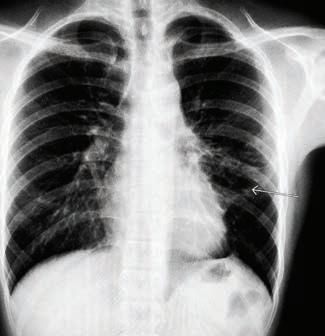

UHN-created tool that supports Emergency Department (ED) physicians in deciding whether to admit or discharge a heart failure patient is now available in Epic, UHN’s electronic patient record system.

The Emergency Heart Failure Mortality Risk Grade (EHMRG) calculator estimates the risk of a heart failure patient dying within one week, and over the course 30 days, based on 13 key metrics calculated in the ED.

Based on the score, different courses of action are recommended depending on a patient’s risk category.

The Epic integration at UHN is the first in Canada for this decision-support tool.

The EHMRG calculator, which was created by Dr. Douglas Lee, a cardiologist at UHN’s Peter Munk Cardiac Centre where he is Ted Rogers Chair in Heart Failure Outcomes, was validated in a clinical trial –“Comparison of Outcomes and Access to Care for Heart Failure (COACH)” – at 10 hospitals across Ontario. The results were in a study published in the New England Journal of Medicine in 2023.

The EMHRG calculator provides a low-risk, intermediate-risk, or highrisk score based on the patient’s presenting metrics at the ED, such as age, blood pressure, creatinine and potassium levels, and whether they arrived by ambulance.

Low-risk patients can be safely discharged from the hospital and given a follow-up appointment with a heart function clinic within two weeks. High-risk individuals should be admitted from the ED for immediate care and ongoing monitoring.

An intermediate-risk score prompts further consultations with hospital specialists to determine if the patient can be discharged with a follow-up appointment within a few days, or should be admitted for monitoring.

It supports clinical decision-making with an objective and evidence-based score – generated automatically and quickly – to help ensure the safety of patients and efficiency of the workflow in a busy ED. This improves patient quality of life, ensures allocation of hospital resources to those in most critical need and reduces health care expenses.

“In the fast-paced environment of Emergency Departments, where decisions can mean the difference between life and death, the Emergency Heart Failure Mortality Risk Grade (EHMRG) score provides timely insights to help make the right decision,” says Dr. Lee, whose work on the project was funded by the Ted Rogers Centre for Heart Research and Institute for Clinical and Evaluative Sciences (ICES).

“Heart failure is complex, and objective measures like the EHM-

RG score can complement physician clinical judgment.”

Before receiving the greenlight for integration into Epic, the EHMRG calculator was first validated in the COACH trial.

The trial at 10 Ontario hospitals saw more than 5,000 patients who came into the ED with acute heart failure divided into two groups. One received usual care, and the other received a special hospital-based strategy using the EHMRG calculator to help physicians determine which patients were able to be safely discharged with follow-up.

The results showed that within 30 days of receiving treatment, the group using the EHMRG calculator had a lower rate of either dying from any cause or being hospitalized again for heart problems compared to the group that received usual care. Over 20 months, the difference in health outcomes between the two groups continued to be better for the EHMRG care group.

Specifically, only the patients in the EHMRG calculator group experienced a statistically significant reduction in death or repeat hospitalization for cardiovascular reasons compared to the control group.

The study concluded that for patients with acute heart failure, receiving care informed by their individual risk level determined with the EHMRG calculator score in tandem with rapid follow-up at a heart function clinic resulted in a lower risk of mortality or re-hospitalization.

It was this promising result that led the Epic and UHN teams to design an integrated care pathway for the ED that incorporated the EHMRG calculator score and integrated it into Epic at multiple UHN sites.

This is the latest tool from the Ted Rogers Centre for Heart Research to be integrated for widescale use across Ontario hospitals, showcasing the incredible impact of both the research and translational work being done by its scientists and clinicians.

“By integrating this calculator into the Epic system at UHN, we’re not just enhancing the decision-making process, we’re helping to transform the way heart failure is managed in the Emergency Department,” says Dr. Lee. “It’s a step forward in our mission to improve the quality of care for heart failure patients across the province.” ■ H